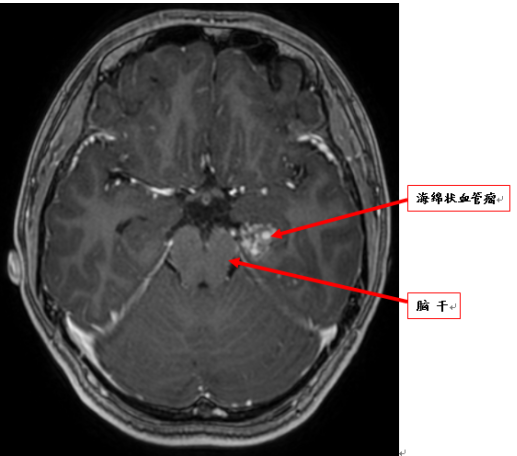

小李的父母闻悉后,带着她到医院做检查,颅脑核磁共振(MRI)发现左颞叶、脑干旁有一病变,考虑海绵状血管瘤。

术前MRI:脑干海绵状血管瘤。